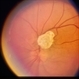

- Fundus camera

- Fundus photograph of a 72-year-old man with a retinal astrocytoma of the left eye.